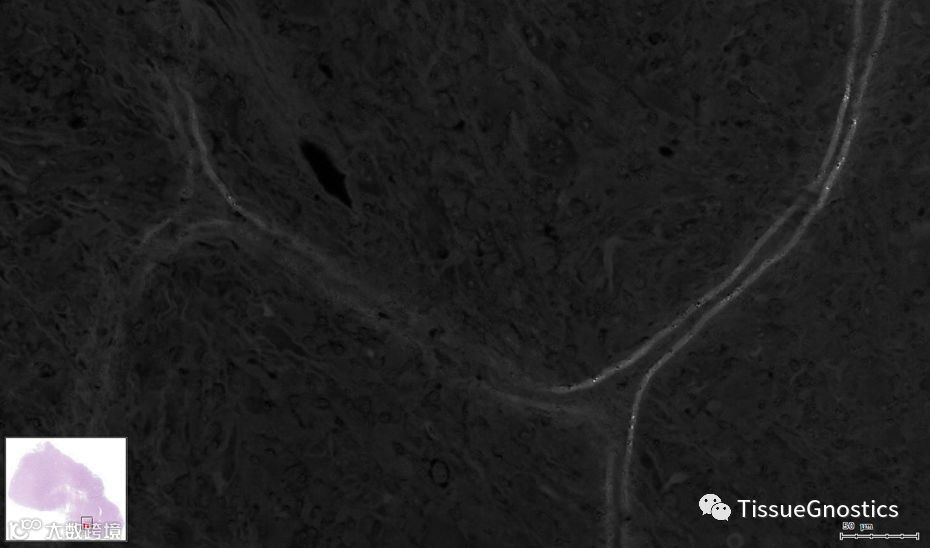

原始影像

伊红染色通道